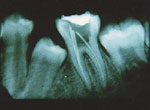

Root Canal Therapy